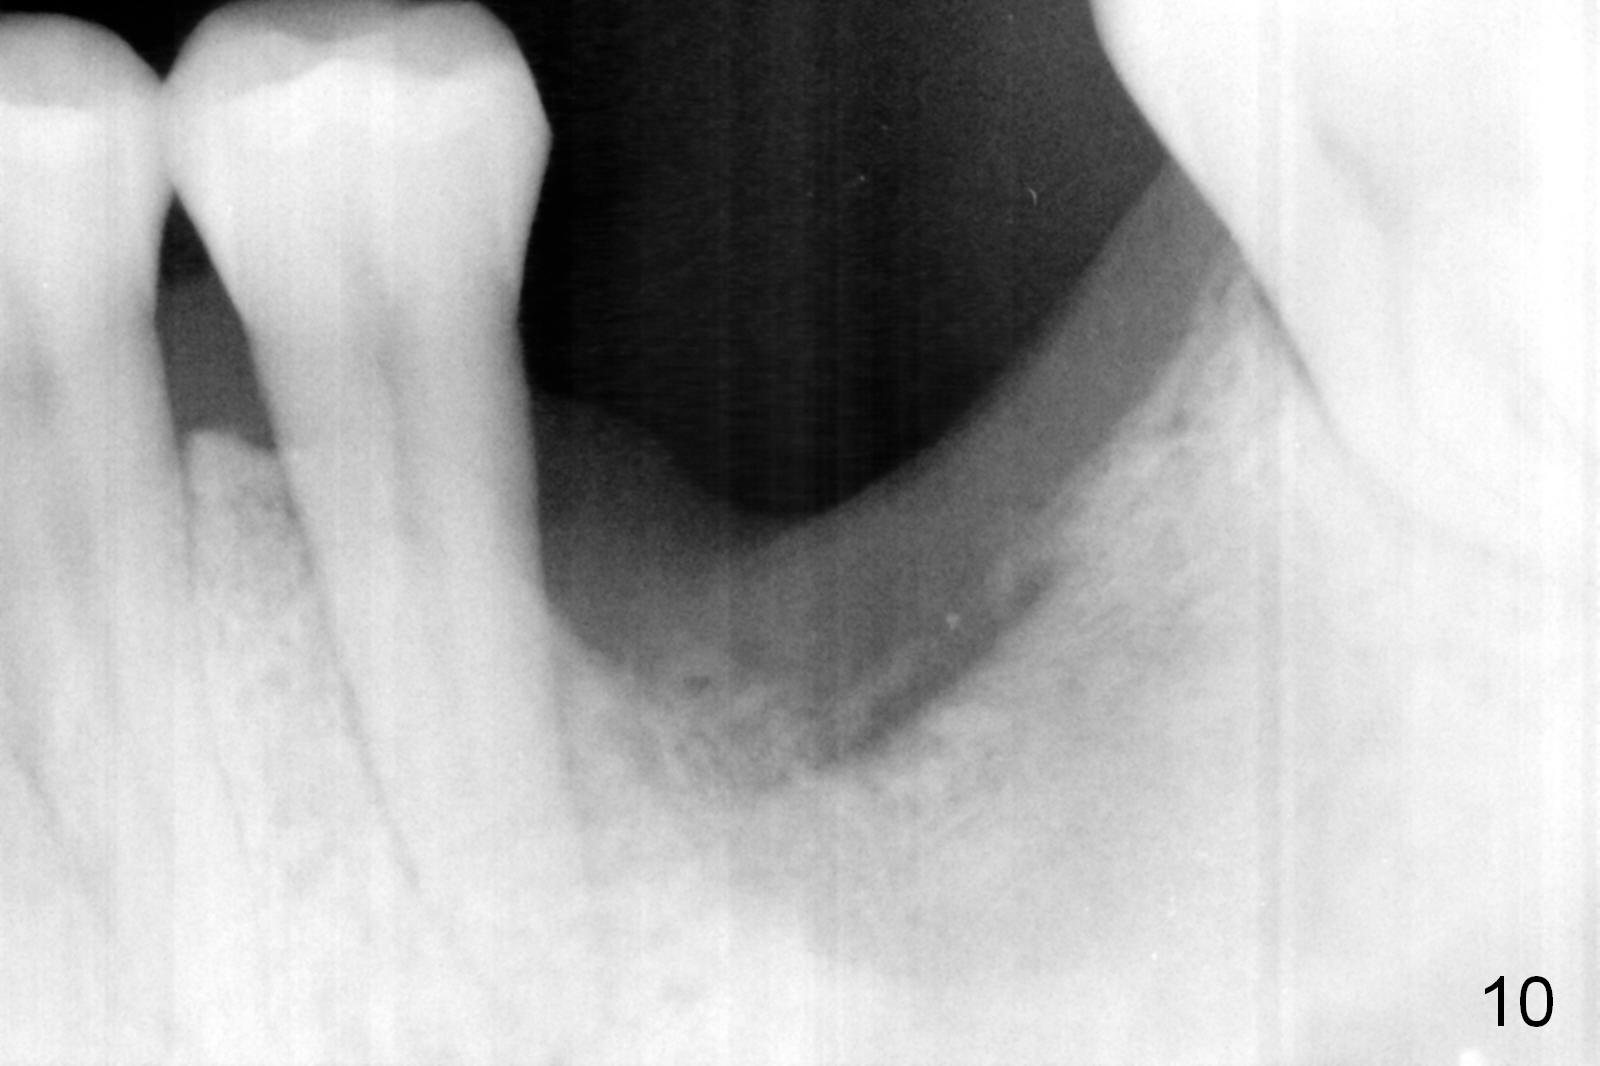

There is bone growth in the mesial socket 5 months post graft (Fig.10). Use Magic Split to get access and test bone density (which must be low or medium in the upper portion). Use drills beyond the socket if necessary. Crown/implant ratio is unfavorable (Fig.11); so progressive loading is essential.